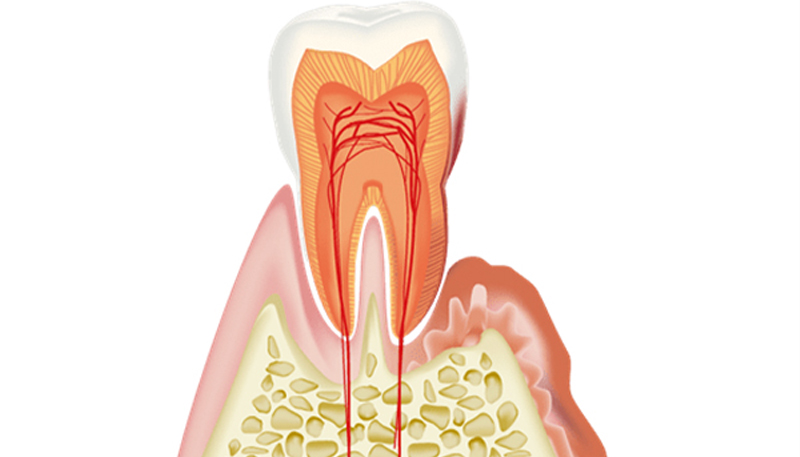

- 歯肉炎

歯肉炎の状態が続く事で、細菌が増えて歯を支える骨が溶けていく病態を言います。

細菌が骨を溶かしているのではなく、細菌に対する私たちの身体の免疫反応の結果骨が溶けていきます。

虫歯のような痛みが出にくいので、定期的な検査とメンテナンスが大切です。

歯周病が原因で抜歯を選択せざるを得ないケースは少なくありません。 歯周病が進行すると、歯と歯肉の間に深い隙間(ポケット)が形成され、そこで細菌が増殖しさらに歯周病を悪化させるという悪循環が生じます。さらに細菌が産生する毒素や、それが原因となる炎症に起因して歯を支える骨も溶けてしまいます。 一般的に、歯周ポケットが6mmを超える状態、また、レントゲン上で歯を支える骨の吸収が大きい場合(歯根の1/3以上)、またそれにより歯のぐらつきが大きい場合は抜歯を考慮しなければなりません。

歯肉に腫れ、出血が見られ、ぐらつきがある場合もあります。歯と歯肉の隙間(ポケット)は深くなっており、汚れやプラーク、歯石が溜まりやすくなっています。

歯肉の上に見えている歯石だけでなく、歯肉の下にも歯石が付着し、歯根を覆っている状態です。

歯石の中に歯周病の原因菌が存在し炎症を引き起こすため、除去する必要がありますが、セルフケアでの除去は困難です。

歯周ポケットが深く、歯肉には腫れや出血、排膿が見られることも多い状態です。歯を支える骨も溶けており、歯のぐらつきもみられます。歯を残すことを第一と考えますが、お口全体の長期的な健康を考え抜歯を選択せざるを得ない場合もあります。